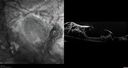

Severe diabetic tractional retinal detachment one year following diagnosis of type II Diabetes Mellitus252 views44 year old man The vision in the left eye started to decline about 4 days ago. Prior to that the left eye was the better eye. He was diagnosed with diabetes a year ago.Â

VA OD: Dcc20/50-1 OS: Dcc20/125-2, TP: OD:12 OS:13

Following two surgeries in each eye, silicone oil remaining forever, monthly anti-VEGF for severe DME - BCVA OU 20/200 at 3 yearsAug 17, 2022